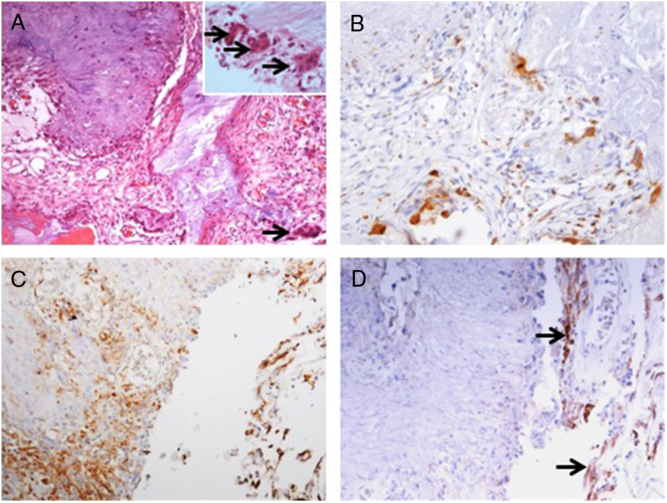

Pathological Findings

Pathology examination confirmed the lesion to be a CAPNON, with cores of granular amorphous materials and peripheral palisading spindle to epithelioid cells, calcification/ossification, and multinucleated giant cells (Figure 4A). Immunohistochemistry demonstrated focally scattered CD68-positive macrophages (Figure 4B), focally positive vimentin in spindle to epithelioid cells (Figure 4C), and limited EMA positivity only in the cells or membranes at the periphery of amorphous core (Figure 4D).

Figure 4: Photomicrographs of the right basal frontal calcifying pseudoneoplasm of the neuraxis. The skull base lesion consisted of cores of granular amorphous materials with peripheral palisading spindle to epithelioid cells, calcification/ossification, and multinucleated giant cells (A, arrows including three in an inset with higher magnification). Immunohistochemistry revealed focally scattered CD68+ macrophages (B), vimentin+ focally in spindle to epithelioid cells (C), and limited EMA+ cells or membranes at periphery of the lesion (D, same area as C; arrows pointing the membranes). Original magnification, ×200 (A–D).

Pathologically, CAPNONs are distinctly different from grossly calcified, psammomatous meningiomas and metaplastic meningiomas. CAPNON is typically composed of the following components: (1) chondromyxoid cores containing amorphous to fibrillary materials; (2) peripheral palisading of spindle to epithelioid cells; (3) calcifications and ossifications; and (4) foreign-body reaction with multinucleated giant cells.Reference Qian, Rubio and Powers23 Despite high variations in these morphological components, the chondromyxoid cores with calcification seem to be a principal constituent of CAPNON. On the other hand, psammomatous meningiomas consist of abundant psammoma bodies (more than half of the tumor) with intermixed meningothelial cells.Reference Liu, Lu and Peng25 Metaplastic meningiomas are characterized by mesenchymal differentiation including osseous, cartilaginous, lipomatus, xanthomatous, and/or myxoid tissue elements, with retained meningothelial cells in nonmetaplastic areas.Reference Caffo, Caruso, Barresi and Tomasello26,Reference Tang, Sun and Chen27 EMA immunostaining, a routinely used marker for meningiomas, is positive largely in the retained meningothelial cells in metaplastic and psammomatous meningiomas. In contrast, CAPNONs have limited EMA positivity that is often linear in distribution and typically seen at the periphery of the amorphous cores or the tissue edge of CAPNONs,Reference Aiken, Akgun, Tihan, Barbaro and Glastonbury3 which may be reflective of the meningeal involvement in the stroma rather than the constituent of CAPNONs. In the 24 reviewed cases of skull base CAPNONs, EMA immunostaining was positive with or without specified distribution in 6 cases (including our 2 cases),Reference Blood, Rodriguez, Nolan, Ramanathan and Desai14,Reference Fletcher, Greenlee, Chang, Smoker, Kirby and O’Brien15,Reference Kerr, Borys, Bobinski and Shahlaie17,Reference Wisniewski, Janczar, Tybor, Papierz and Jaskolski24 but negative in 2 cases,Reference Hodges, Karikari and Nimjee16,Reference Nussbaum, Hilton and Defillo20 and not mentioned in the remaining 16 cases. We speculate that EMA is usually negative in CAPNONs without the meningeal involvement or focally positive in CAPNONs with the meningeal involvement, and its positivity is limited to the meningothelial cells entrapped in CAPNON lesions. Therefore, EMA is a useful pathological marker to differentiate CAPNONs from calcified psammomatous or metaplastic meningiomas (Table 2).